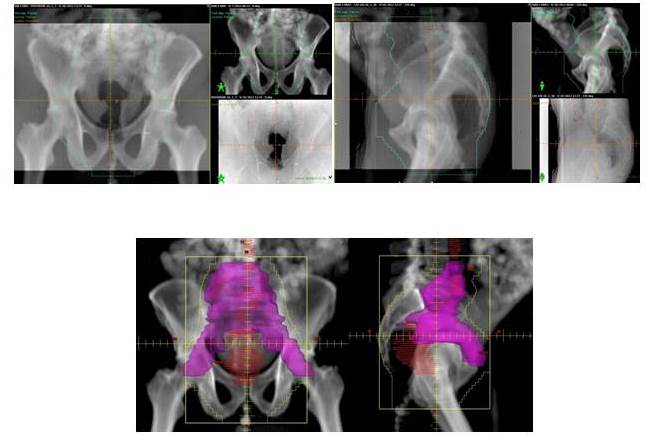

En cuanto a la RT, la técnica más utilizada fue la conformada con planificación tridimensional (RTC 3D), sólo en 3 pacientes se empleó la técnica de intensidad modulada (RTIM). Se utilizaron 4 campos, dos laterales, uno anterior y otro posterior, que inicialmente incluían toda la pelvis, con fracciones diarias de 180-200 cGy hasta una dosis de 4 500-4 600 cGy, realizando posteriormente reducción al sitio de lesión macroscópica (RT neoadyuvante) o al área de anastomosis (RT adyuvante) hasta completar 5 000-5 040cGy (Cuadro 1 y Figura 1-4).